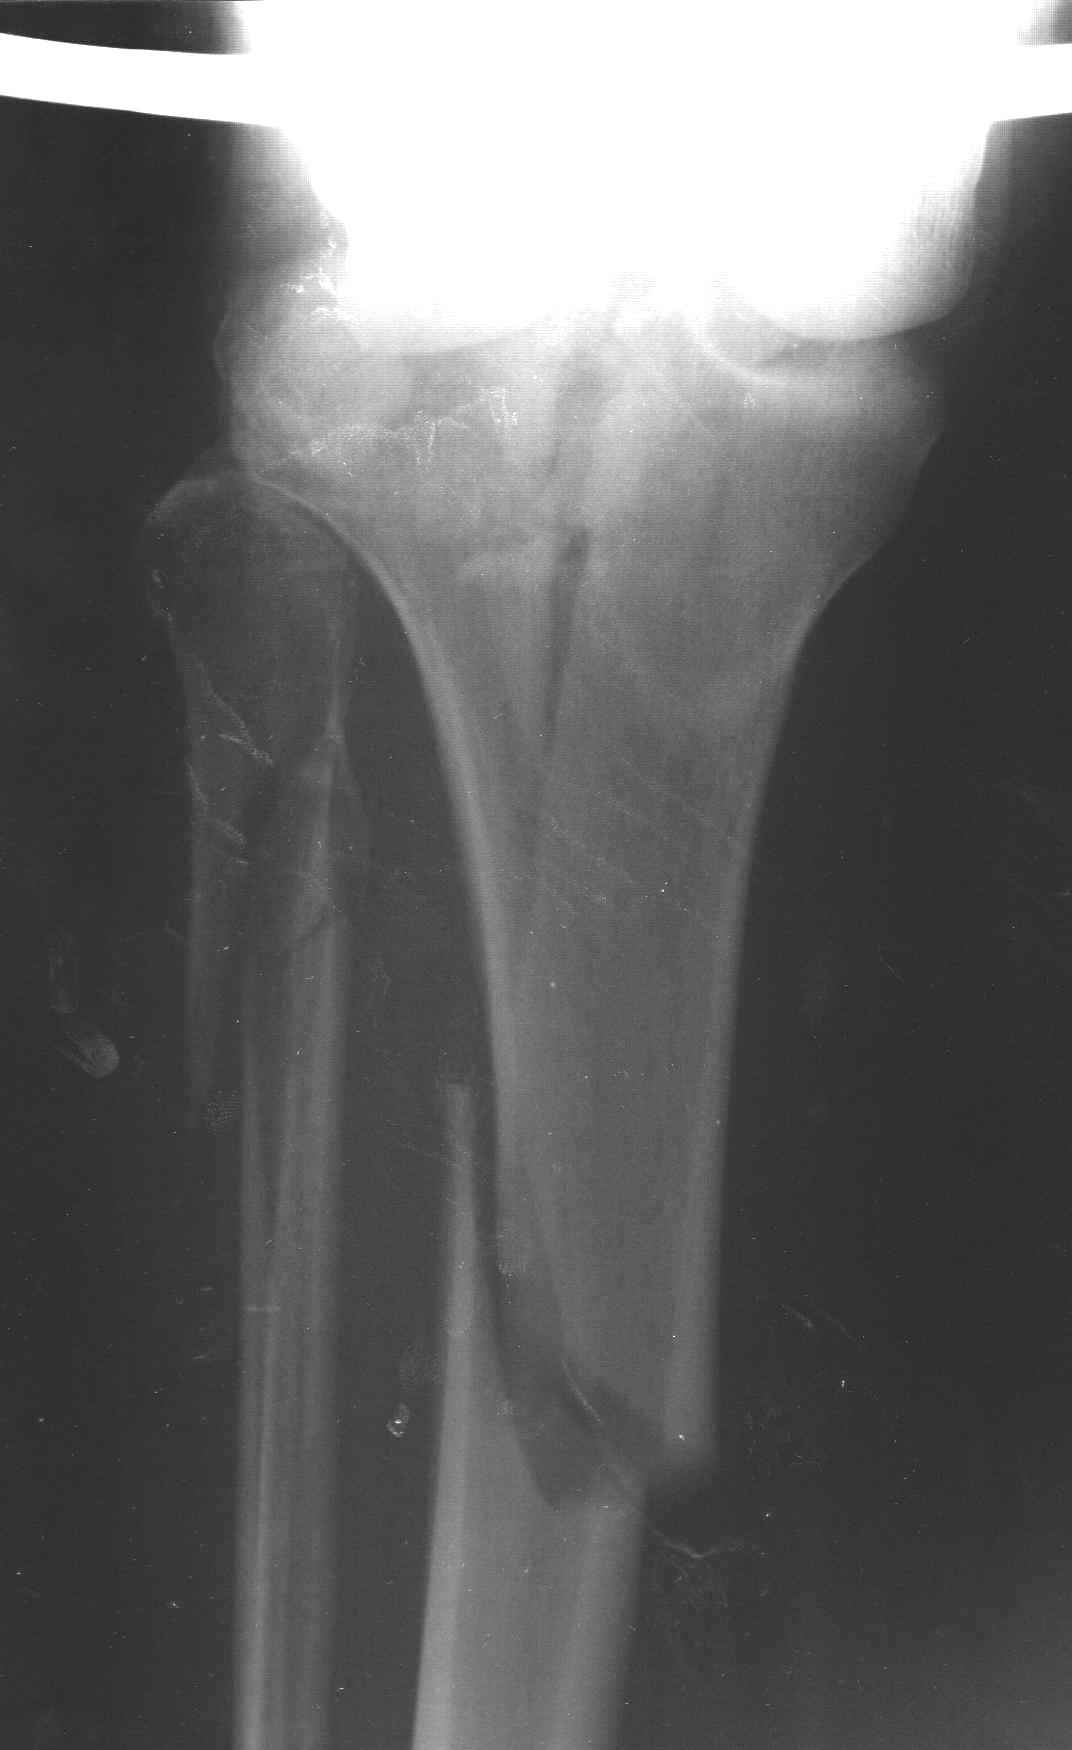

АЛ> Интересует срок проведения оперативного вмешательства,

АЛ> оптимальный выбор фиксатора (особенно интересует возможность БИОС

Интрамедуллярный остеосинтез диафизарного перелома тут возможен, но в первую очередь надо с помощью КТ уточнить повреждение суставного конца. Импрессионный перелом наружного мыщелка явный есть, может, и медиальная колонна повреждена, так что надо в первую очередь планировать открытую репозицию с замещением дефекта с фиксацией пластиной или аппаратом. Если получается технически, можно поверх уже синтезированного стержнем диафиза.

Уважаемый Александр Николаевич! Прошу прощения за некачественные сканы. КТ вообще-то реально, но сложности с транспортировкой больного в соседний корпус (такая перевозка и перекладывание для больных - дополнительная травма). По Р-граммам медиальный отдел вроде целый, но наружный мыщелок "отклячен" и суставная поверхность явно просела. У нас весь вопрос в методе фиксации или же их сочетании - одна пластина, опорная пластина и стержень (я так понял, что вы предлагаете сначала фиксировать диафиз, а потом заняться мыщелком?), винты и стержень, аппарат...Опять же состояние м/тканей (плотный отек, кровоизлияние)...